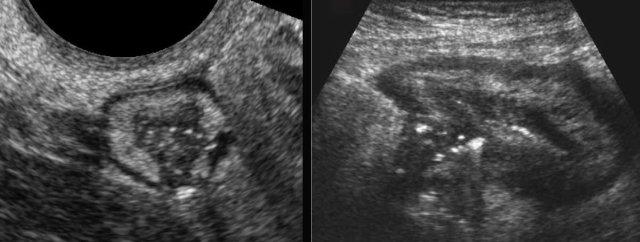

Loét

Các ổ sáng lệch tâm nằm trong vùng giảm âm là hình ảnh khí biểu hiện cho loét sâu, được mô tả ở đây trên hai bệnh nhân khác nhau.

Các vết loét xuyên thành này báo hiệu sự hình thành đường xoang, áp xe và rò.

Lưu ý mô mỡ viêm bao quanh một phần, đại diện cho mạc treo và mạc nối, đang bao bọc hiệu quả vị trí thủng sắp xảy ra.